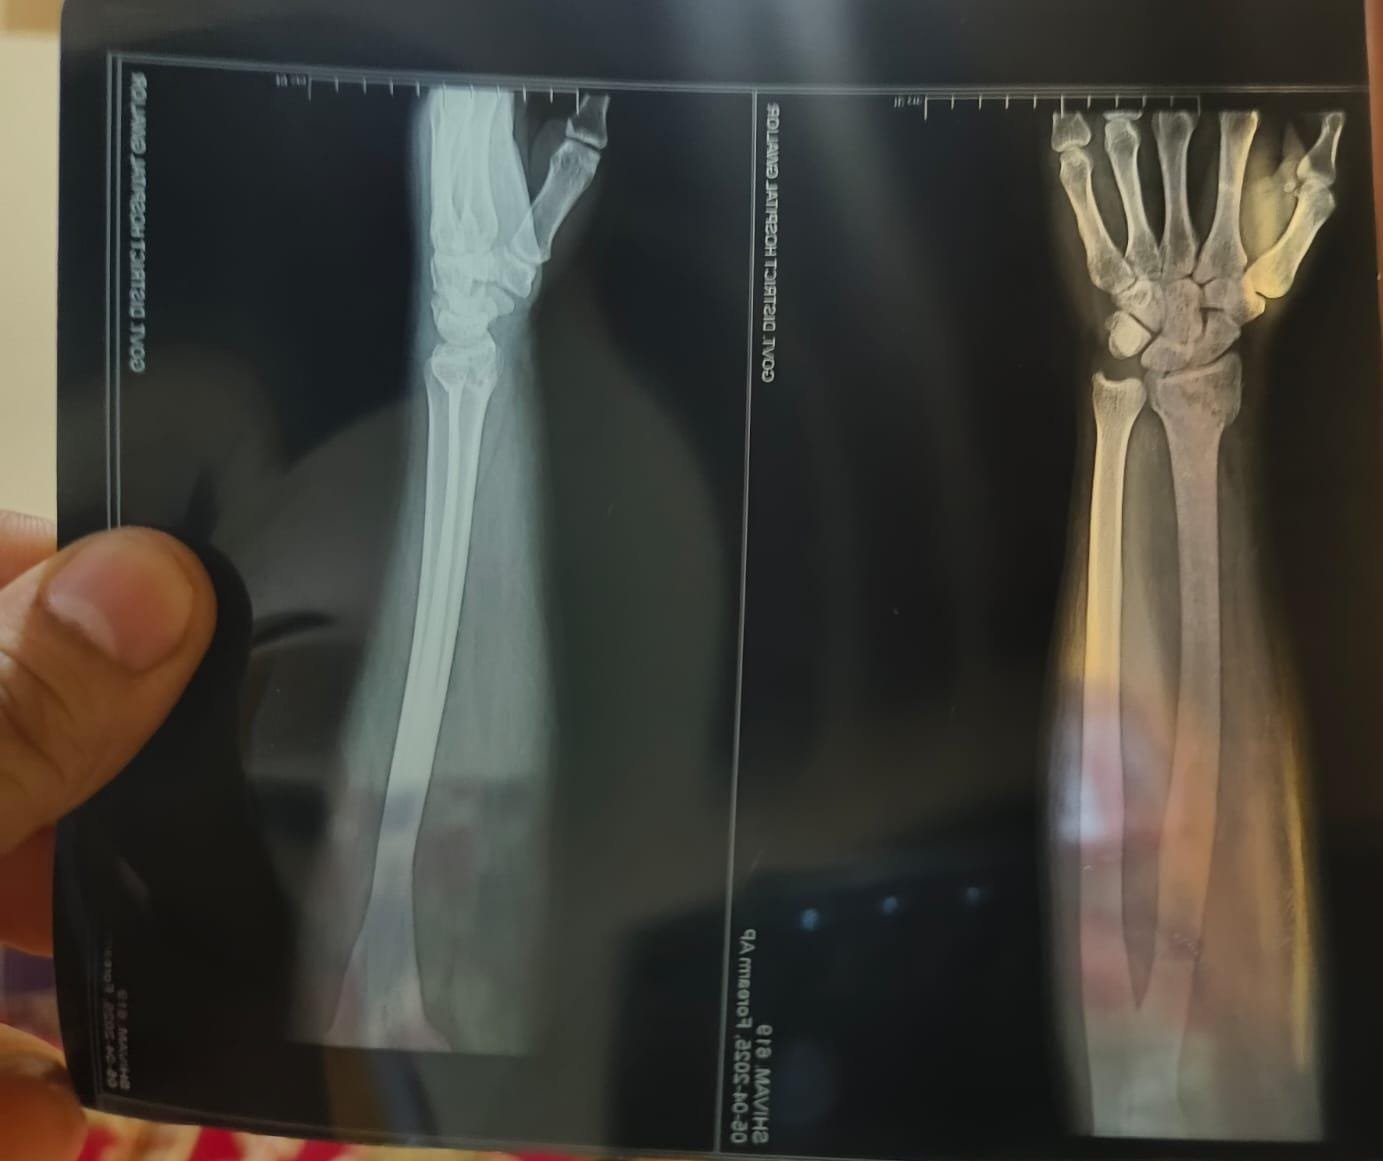

भिंड। भिंड मे खोया व्यापारी के साथ हुई मारपीट।पड़ोसी दुकानदार ने खोया व्यापारी से की मारपीट।दुकान मे घुसकर व्यापारी के साथ पड़ोसी दुकानदार ने की मारपीट।पड़ोसी दुकानदार ने अपने सहयोगी साथी व पत्नी के साथ एकराय होकर बोला हमला, लोहे के सरिया व डंडे से की मारपीट।खोया दुकानदार के साथ मारपीट किए जानें का वीडियो सामने घर पर लगे CCTV कैमरे मे हुआ कैद, अब हो रहा वायरल।मारपीट के दौरान लोहे का सरिया लगने से खोया व्यापारी का दाहिना हाथ हुआ फ्रैक्चर, अन्य जगह भी लगी चोट।

मारपीट के समय खोया व्यापारी व उनके पिता अपने दुकान पर थे बैठे, अचानक पड़ोसी व्यापारी ने बोला हमला।घटना भिंड के सिटी कोतवाली थाना क्षेत्र अंतर्गत पुस्तक बाजार अम्बेडकर मार्केट की बीते 31 मार्च देर शाम की है।घटना के बाद सिटी कोतवाली थाना पहुंचकर खोया व्यापारी ने आरोपी पड़ोसी दुकानदार पर दर्ज कराई FIR।FIR होने के लगभग 5 दिन बाद भी पुलिस ने हाथ फ्रैक्चर होने की FIR मे नहीं बढ़ाई धारा, पीड़ित व्यापारी थाने के काट रहा चक्कर।पीड़ित खोया व्यापारी लगा रहा गुहार, पड़ोसी दुकानदार की पत्नी जान से मरवाने की दे रही अभी भी धमकी।